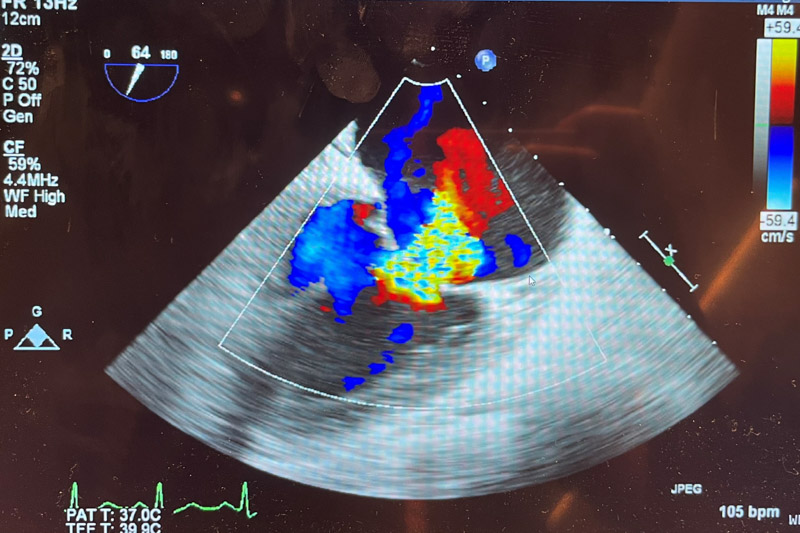

韋阿姨在當地治療了一段時間,癥狀并沒有好轉,隨后,在柳州工作的兒子陪同她來到柳州市人民醫院心血管內科就診。檢查發現,患者二尖瓣前葉脫垂并重度關閉不全(反流面積10.7cm2),左室壁運動普遍減低(EF48%),情況非常嚴重,救治刻不容緩!

充分完善術前評估后,8月19日上午,在阜外醫院潘湘斌教授及超聲醫生鄧燕技術支持下,順利將手術系統送入患者左心房,到達二尖瓣A2P2反流處,反復評估二尖瓣反流位置、抓捕位置、反流程度,精準夾合,成功植入1個二尖瓣夾。術后患者反流情況明顯改善,跨瓣平均壓差2mmHg,其他各項生理指標正常,反流改善明顯,術前反流4+,術后反流小于1+,手術順利完成。